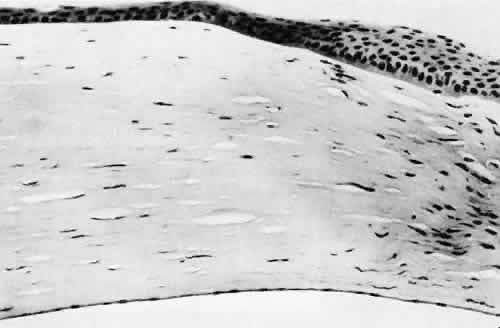

Corneal endothelial decompensation (Fig. 36) may lead to bullous keratopathy at almost any time in the postoperative period, depending on the state of health of the endothelium at the time of surgery and the extent and nature of injury to the endothelial cells.110,111 Corneal edema may present early in the postoperative period when the cornea has been compromised by advanced Fuchs corneal dystrophy. If the endothelial cells are healthy and the intraoperative trauma is minimal, the signs of decompensation may not appear for decades. Endothelial damage may be the result of mechanical contact with surgical instruments or an intraocular lens, a toxic reaction to solutions used intraoperatively, poor tissue handling techniques, or prolonged and intensive postoperative inflammation.112 Histologically, the corneal epithelium is generally thinned. There may be areas of intraepithelial basement membrane and cyst formation, resulting from malorientation of the squamous epithelial cells during recovery from multiple episodes of bullous separation from Bowman's membrane (Fig. 37). Bullous separation of the epithelial cells varies in extent but is almost always present. Focal areas of interruption of Bowman's membrane and anterior corneal stroma scarring will mark rupture of bullae and subsequent ulceration. In chronic cases, extensive degenerative pannus formation is often seen. The corneal stroma may show a decreased density of keratocyte nuclei. A decrease in or absence of the artifactual clefts of the corneal stromal lamellae suggests edema of the stroma. Descemet's membrane may be focally or diffusely thickened with preexisting Fuchs corneal dystrophy (Fig. 38). In most cases, Descemet's membrane is normal in character and thickness. Often the corneal endothelial density is reduced to the point that only an occasional endothelial cell nucleus can be seen.

Fig. 36. Light micrograph of a corneal specimen removed because of bullous keratopathy. Descemet's membrane (arrow) is of normal caliber and character for the patient's age. No endothelial cells can be identified at the light microscopic level. Because of the normal caliber of Descemet's membrane, the endothelial cell change appears to be of short duration and is attributed to problems associated with pseudophakia (pseudophakic bullous keratopathy). (Periodic acid-Schiff stain; × 100.)